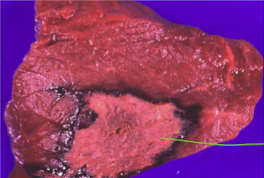

What is the pattern of necrosis that is shown below?

Massive necrosis - usually a toxic or nutritional cause